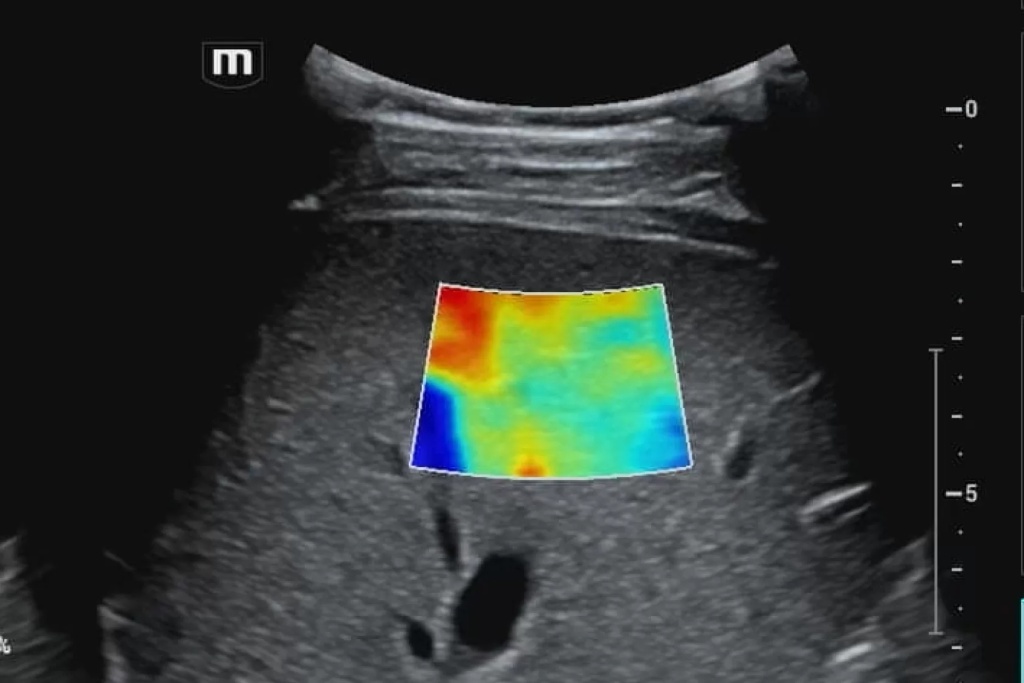

Для улучшения качества УЗИ изображений был разработан режим тканевой гармоники. Эта технология основана на выделении гармонической составляющей ультразвуковых колебаний, которые возникают в тканях при прохождении через них ультразвукового сигнала.

Роль режима тканевой гармоники в медицинской диагностике, несомненно, критическая. Этот метод ультразвукового исследования обеспечивает высокую разрешающую способность, позволяя врачам более точно выявлять структурные изменения в органах и тканях. Применение тканевой гармоники в онкологии, например, значительно повышает точность обнаружения опухолей и улучшает оценку их характеристик.

Режим тканевой гармоники в медицинской диагностике базируется на использовании высокочастотных звуковых волн, которые позволяют лучше проникнуть в ткани организма. Этот метод улучшает разрешение изображения и способен выделять структурные особенности тканей, что особенно важно при обследовании органов с различной плотностью.

Принцип работы режима тканевой гармоники можно объяснить следующим образом. Ультразвуковой сигнал, посылаемый датчиком УЗИ-аппарата, имеет определенную частоту. При прохождении через ткани этот сигнал вызывает колебания этих тканей. Колебания тканей также имеют определенную частоту, но она в два раза выше частоты исходного сигнала.

Гармоническая составляющая ультразвуковых колебаний — это та часть колебаний, частота которой в два раза выше частоты исходного сигнала. Режим тканевой гармоники позволяет выделить эту составляющую из отраженного от тканей сигнала.

1. Улучшенное контрастное разрешение. Это означает, что на изображениях, полученных в режиме тканевой гармоники, различные ткани и структуры более четко различимы. Это связано с тем, что в режиме тканевой гармоники подавляются артефакты, которые могут маскировать мелкие детали.

2. Уменьшение артефактов. Артефакты — это искажения изображения, которые могут затруднять диагностику. Режим тканевой гармоники позволяет уменьшить количество артефактов, что улучшает качество изображения.

3. Увеличение глубины проникновения. Режим тканевой гармоники позволяет получать более четкие изображения органов, расположенных глубоко в теле. Это связано с тем, что в режиме тканевой гармоники ультразвуковые волны поглощаются тканями меньше, чем в традиционных режимах УЗИ.